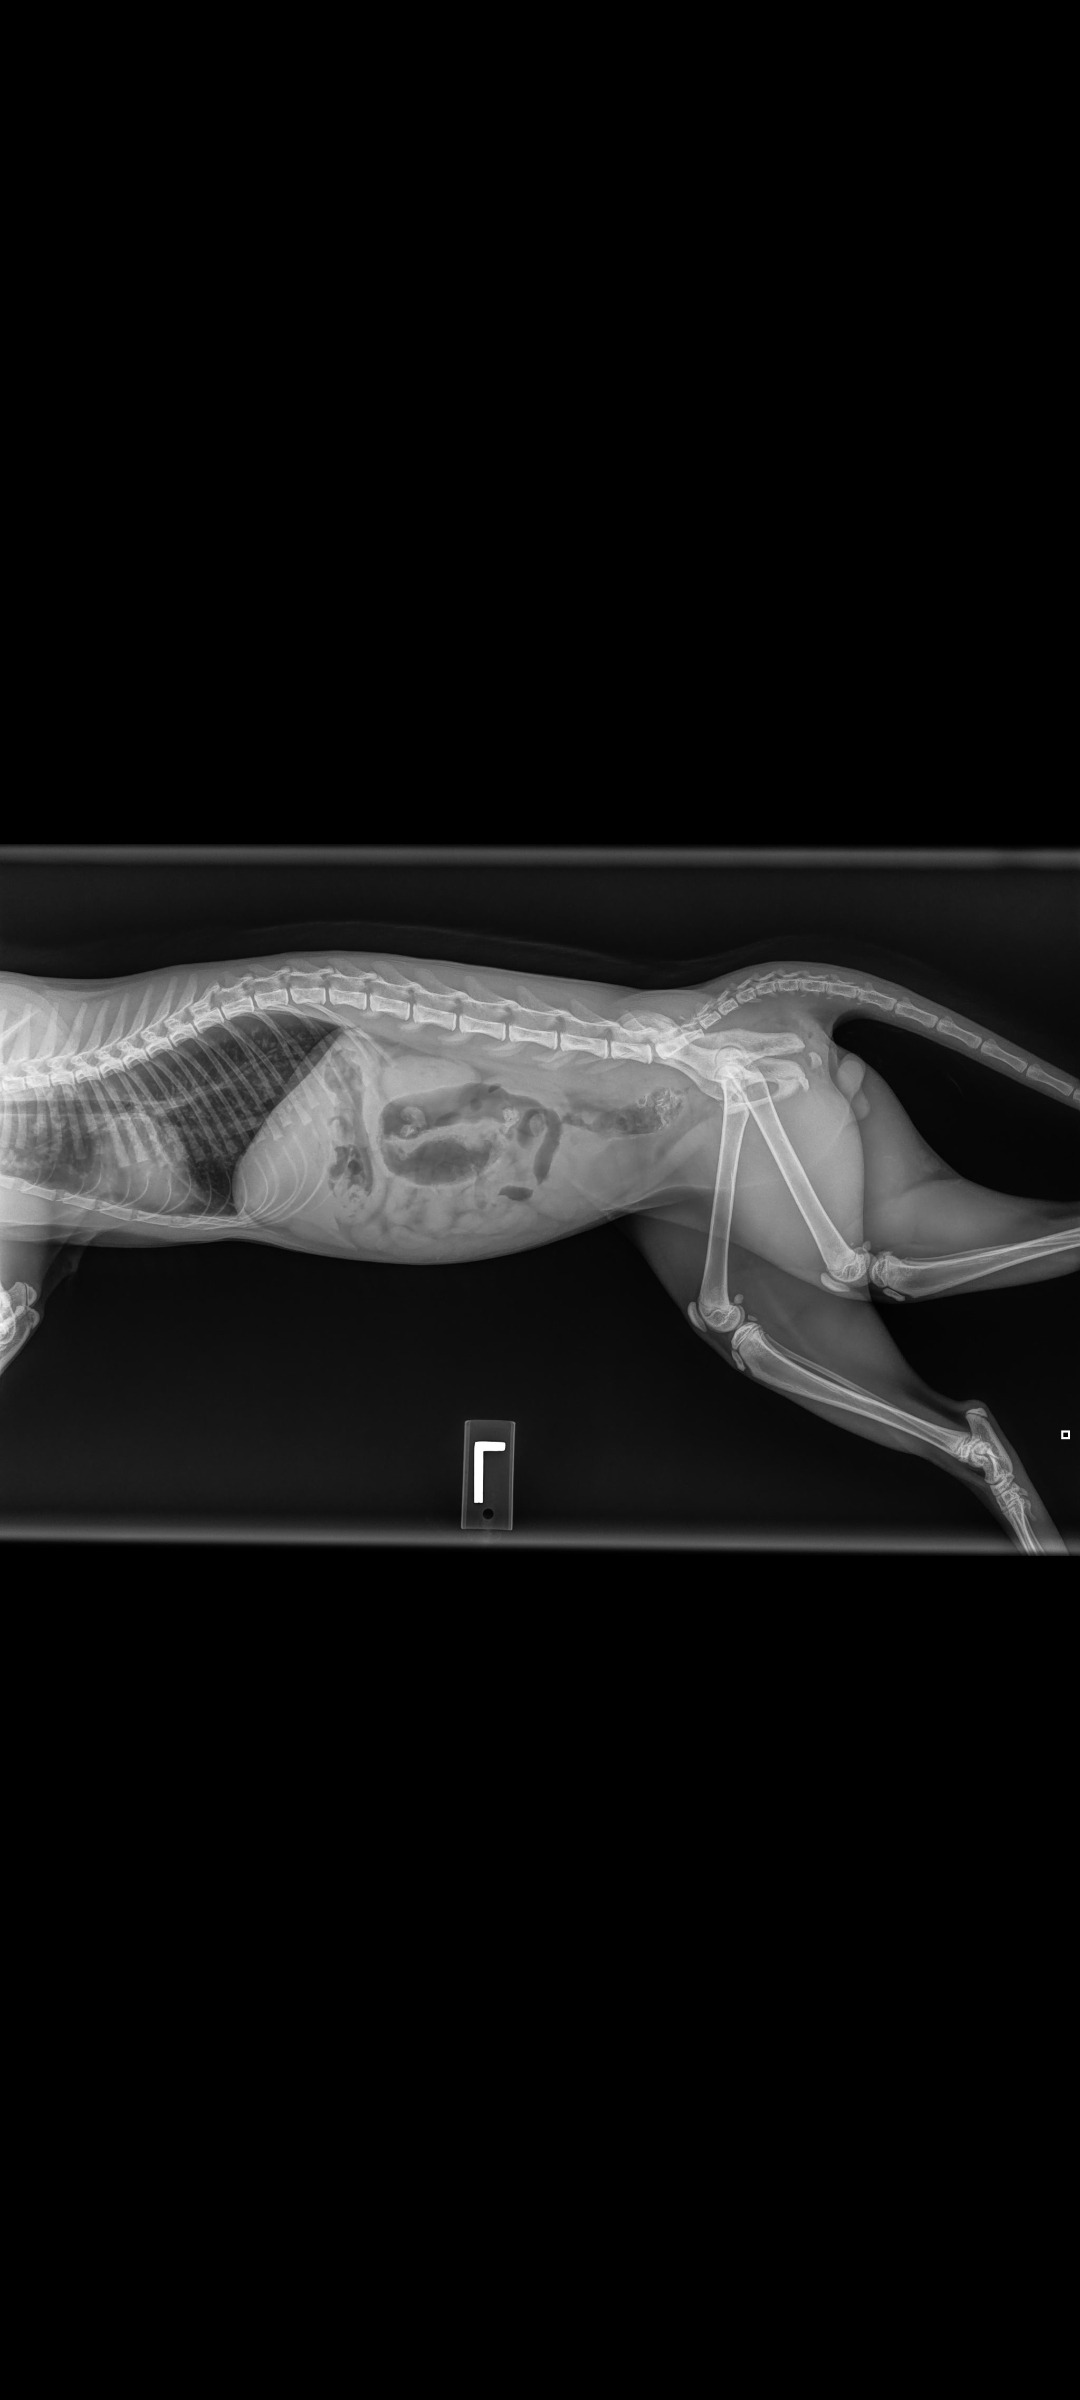

He has pretty banged up and bruised lungs, which is a huge concern. He has to be closely monitored to watch that the blood pockets in his lungs don't pop, which means more scans.

He also has a fractured/broken pelvis. He is unable to walk. He is crate/cage bound for 2 weeks to minimize any movement in hopes that it heals properly but will also require physical therapy and more scans and x-rays.